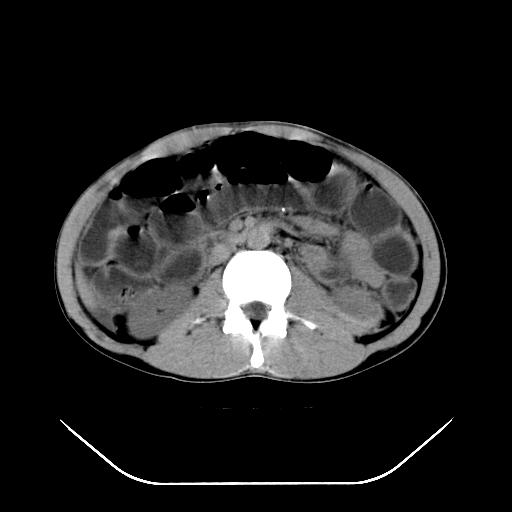

m-25y 高空堕落 12 月5号

12月7号病人尿量200ml/24h 急查双肾ct

左肾挫裂伤并肾周血肿;

左肾挫裂伤并肾周血肿

支持 : 左肾挫裂伤并肾周血肿

支持:1、左肾挫裂伤并肾周血肿;

2、少量腹水;

3、左肾旋转不良;

4、反射性肠淤张。

3、反射性肠淤张。

综上所述,考虑1:左肾挫伤并包膜下血肿2:少量腹腔积液3:肠梗阻的可能

除了1:左肾挫裂伤并肾周血肿;

2:少量腹水

第二次ct检查后:临床医生腹水穿刺后考虑肠系膜动脉破裂,后实行剖腹探查:于空肠距离十二指肠90cm处发现肠管破裂,破裂口较小;修补后关腹。